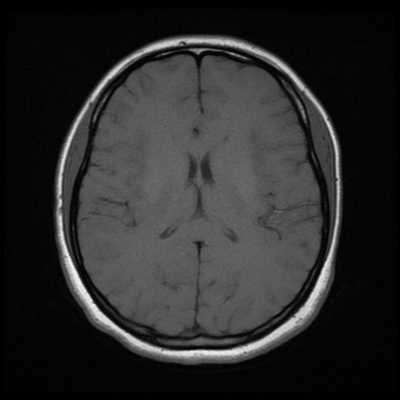

Классический пример МРТ снимков головного мозга показан на рисунках ниже. Магнитно-резонансная томография выполняется в поперечной (или аксиальной - рисунок снизу) и продольной (или сагиттальной — рисунок сверху) плоскостях.

Исследование выполняется в нескольких режимах. Основные из них Т1 и Т2. Изображения, полученные в данных режимах, часто также называют Т1-взвешенными или Т2-взвешенными снимками. Изображения, показанные выше, сделаны в Т1-режиме.

Главное отличие этих режимов - в том, как на снимках отображается жидкость и воздух. В Т1 режиме ткани, содержащие большое количество воды, имеют более темную окраску, в то время как в Т2 режиме они яркие, светлые. Это легко понять, посмотрев на снимки выше - глазные яблоки визуализируются в виде светлых парных округлых образований с одной стороны яркие и светлые, с другой - темные. Следовательно, снимок справа сделан в Т1 режиме, снимок слева - в Т2. Также существует разница в том, как в этих режимах отображается серое вещество головного мозга. В Т2 режиме оно светлее, чем белое вещество.

Как же узнать, есть ли на снимках признаки болезни? Самое главное - запомнить, как выглядит головной мозг здорового человека. Врач, изучая снимки пациентов, постоянно сравнивает их с нормальными снимками, хранящимися у него в голове. Чтобы понять, как это происходит - посмотрите на снимки внизу:

Перед вами - два снимка, сделанных в одном режиме. Снимок снизу - норма. Какое заболевание, в таком случае, есть на верхнем снимке? Чтобы понять это, нужно сравнить эти изображения. Явно видно отличие - на верхнем снимке в правой части головного мозга есть новообразование. Разница еще заметнее, если сравнить левую и правую части того же снимка.